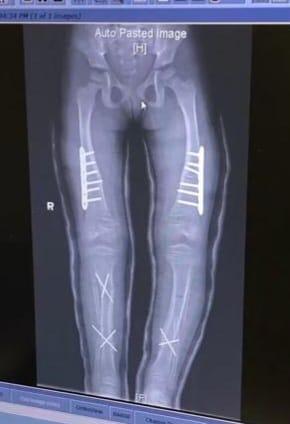

現年12歲的Kelly,自小常常跌倒,輾轉確診XLH,因體內的磷酸鹽大量流失,影響全身骨骼生長。但傳統藥物口服磷酸鹽的療效欠佳,她雙腳愈來愈彎,出現O形腳,至2018年首次接受⼿術,要將⼤腿骨及⼩腿骨折斷,加裝鋼條固定位置,再重新駁骨。然而缺磷問題未解決,歷年做過五次折骨、駁骨或拆鋼條等大⼿術。

Kelly接受第一次O型腳矯正手術後的X光片